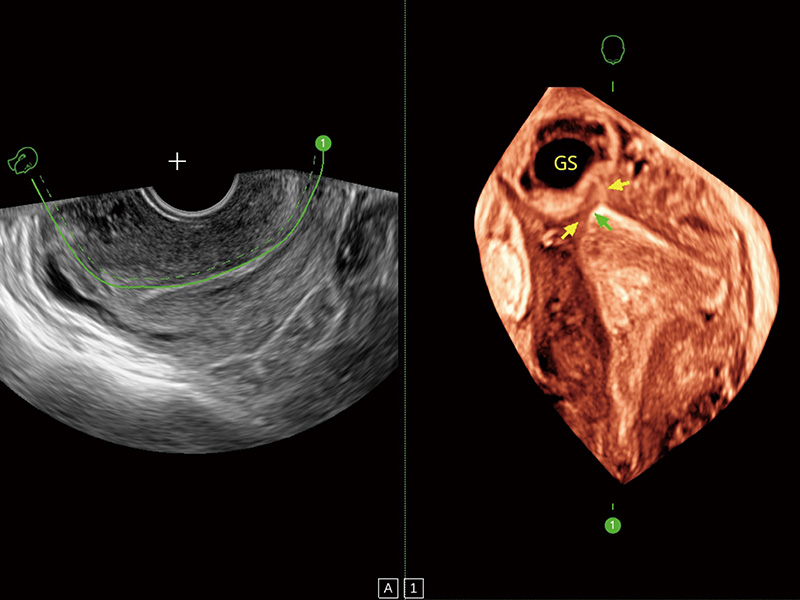

超声引导下胚胎移植

腔内三维成像技术获得显著提升,超大扇角在满足日常基础扫查的同时,支持卵泡自动测量及多种三维渲染模式,为您提供更多的诊断信息,尤其是在子宫畸形的诊断,内膜及肿瘤占位观测中起到了重要的作用。